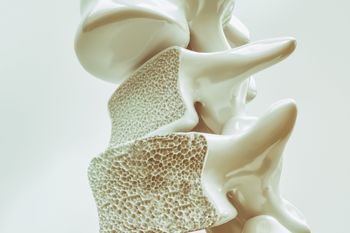

TeleECHO educational programs for healthcare providers have successfully trained physicians and other healthcare providers to fulfill the unmet needs of patients without access to specialty care, particularly osteoporosis care. In this interview with Dr. Michael Lewiecki, he introduces us to Bone Health TeleECHO. He tells us how the program works, why it’s needed and how you can launch one in your state.